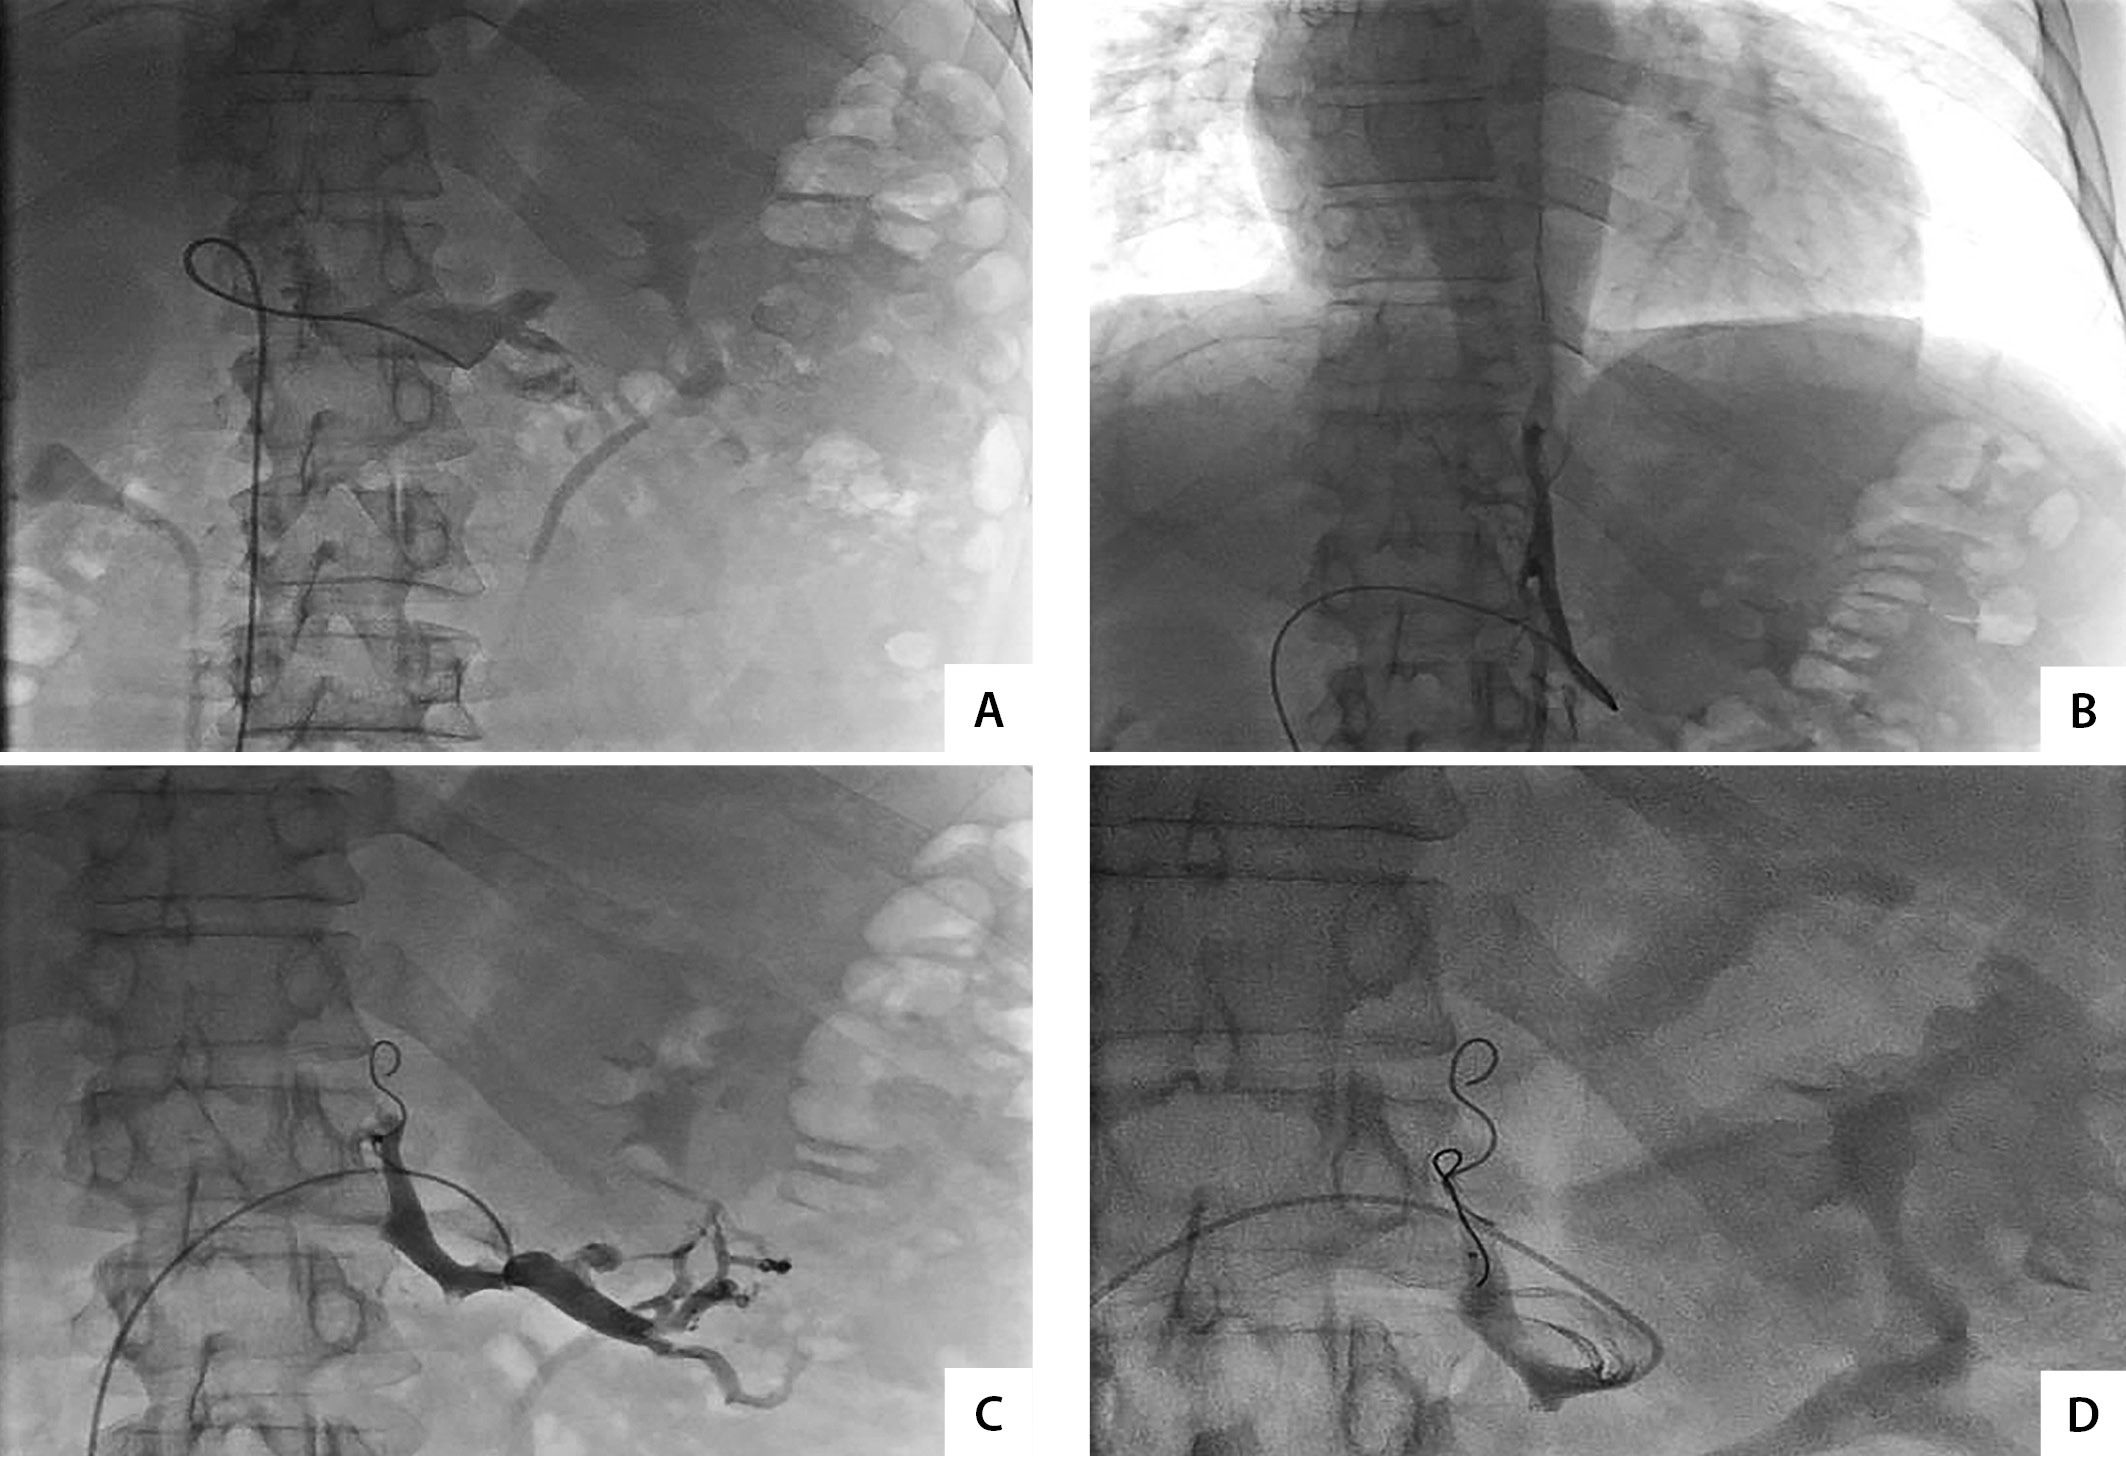

2. Figure 2. Arterial stage of endovascular intervention: A - selective angiography of the left middle adrenal artery; C - complete reduction of blood flow in the left middle adrenal artery after embolization with polyvinyl alcohol particles. | |

3. Figure 3. Venous phase of X-ray endovascular intervention: A - construction of the left renal vein and the mouth of the left adrenal vein; B - selective angiography of the central vein of the adrenal gland; C - contrasting of the left renal vein and central adrenal vein after implantation of the occluding coil; D - after implantation of the second coil, there is no contrasting of the central vein of the left adrenal gland. | |